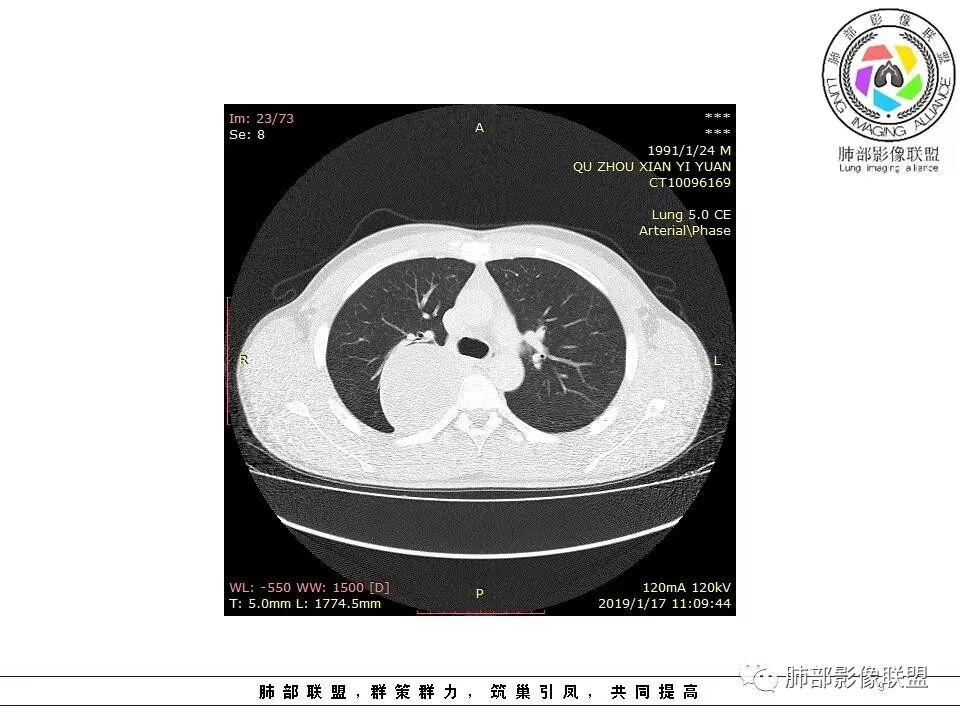

右后纵膈脊柱旁软组织占位,形态规则类圆,边缘光整,肺组织受压,胸膜尾,肋间动脉供血。中度不均匀延迟强化。

后纵隔脊柱旁占位性病变,疾病谱有神经鞘瘤,sft,节细胞瘤,髓外造血。此例有胸膜尾征,蛇纹征 ,延迟强化。考虑胸膜孤立性纤维瘤。看到有供血动脉,但不知道是哪里的血管。

后纵隔类圆形新生物,边缘光滑,胸膜尾征明显,贴近脊柱,蛇纹,血供丰富,考虑后纵隔软组织肿瘤,具体类型看不出来,鉴别神经鞘瘤。

右后纵膈脊柱旁软组织占位,边界清晰,光整,肺组织受压。胸膜被掀起,肋间动脉供血,中度不均匀延迟强化。考虑神经鞘瘤,不除外纤维瘤

右后纵膈脊柱旁软组织影,与纵隔结构分界不清,形态规则类圆,边缘光整,肺组织受压,胸膜尾,肋间动脉供血。肺动脉推移,中度不均匀延迟强化。考虑神经来源,神经鞘瘤,神经纤维瘤二者不易鉴别。

青年男性,间断胸痛;右侧脊柱旁可见一类圆形软组织密度影,密度欠均匀,增强扫描呈轻中度持续强化,邻近肺组织及肺动脉推移,可见肋间动脉供血,部分胸膜下脂肪可见,部分层面似见与右侧椎间孔相连。考虑后纵隔神经源性肿瘤。

1.右上胸内脊柱旁类圆形肿块,质地似乎比较坚实,密度稍显不均,但未显示明确的坏死。

如此密度形态的病灶位于肺边缘首先应当想到孤立性纤维瘤,可相邻胸膜未见明显的异常强化和胸膜方向延伸。

注意所谓“胸膜尾征”的概念及形成机制与“脑膜尾征”是大不相同的。

2.肋间动脉病供血也提示肿块来自后纵隔?

3.相邻椎间孔未见扩大,也未见块影延入椎管,易起自于神经根的鞘瘤似乎找不到支持点。

可惜未提供矢状位骨窗图像,如在肋骨内下缘观察到压迹有助于肋间神经的鞘瘤的判断,这是因为二者之间密切的毗邻关系。

4.静脉期轻度不均匀强化,注意不是环形强化,亦未见明确的“AB区”,这点也不支持神经鞘瘤。临床及病灶轻度强化都不支持副节瘤。